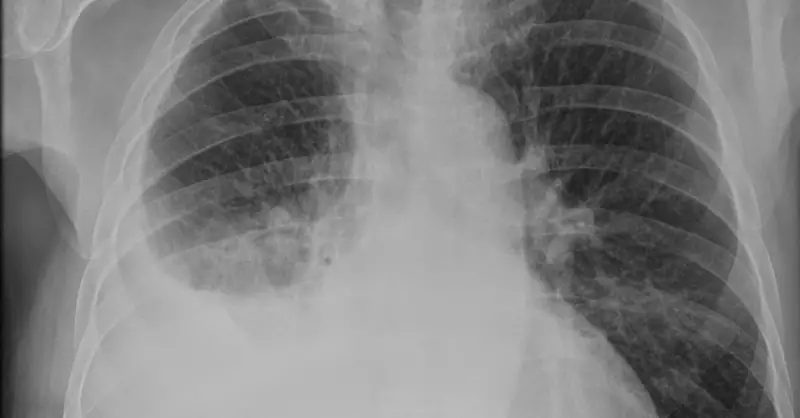

Hastalığın teşhisinde göğüs röntgeni, bilgisayarlı tomografi ve ultrasonografi gibi görüntüleme yöntemleri kullanılır. Gerektiğinde, torasentez işlemiyle sıvı örneği alınarak laboratuvar analizi yapılır.